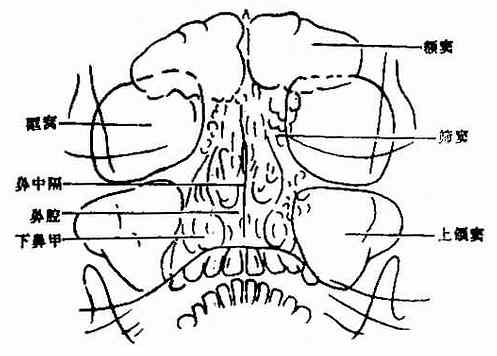

正常影像(图2-18):

图2-18 正常副鼻窦,华氏位(Water)

上颌窦 位于鼻腔两侧,为倒置的三角形透光区,左右大致,骨壁清楚,粘膜可不显影或为沿窦壁厚度不超过1mm的软组织影。

额窦位于两眼眶的内上方,左右各一,不一定对称,正常额窦气化程度差异大,气化良好的额窦略呈花瓣状。

筛窦位于鼻腔和两眼眶间的小蜂窝状影,为筛窦前群。筛窦后群在此位置中位于眼眶内下方并与鼻腔侧壁重迭,不易观察。

蝶窦 因与上、下颌骨重迭而不易观察,常用颏顶位检查。